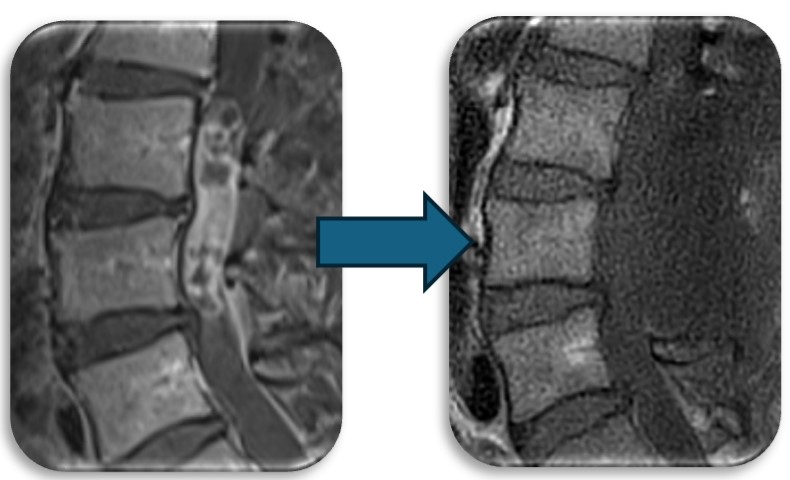

(代表例)

腰部の馬尾神経に発生した神経鞘腫の症例。脊髄腫瘍としては比較的多く割合を占める神経鞘腫は良性腫瘍であり、基本的には全摘出が可能で予後も良好です。この症例も坐骨神経痛と間欠跛行という馬尾障害の症状を呈していましたが、術後は改善し再発も認めておりません。